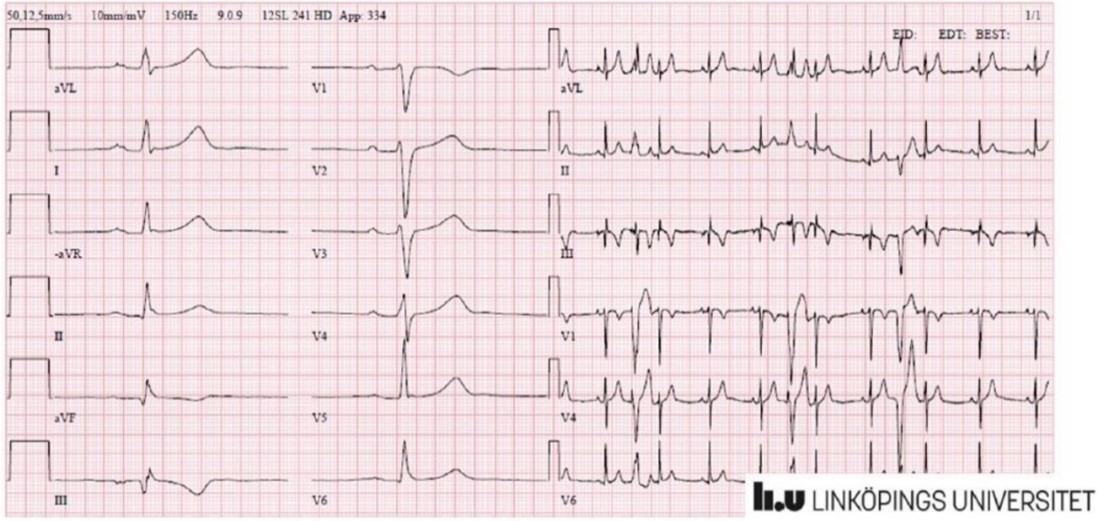

EKG

- Något långsam sinusrytm med frekventa VES

- Förändringar förenliga med en inferior infarkt

- Inget tidigare EKG finns för jämförelse